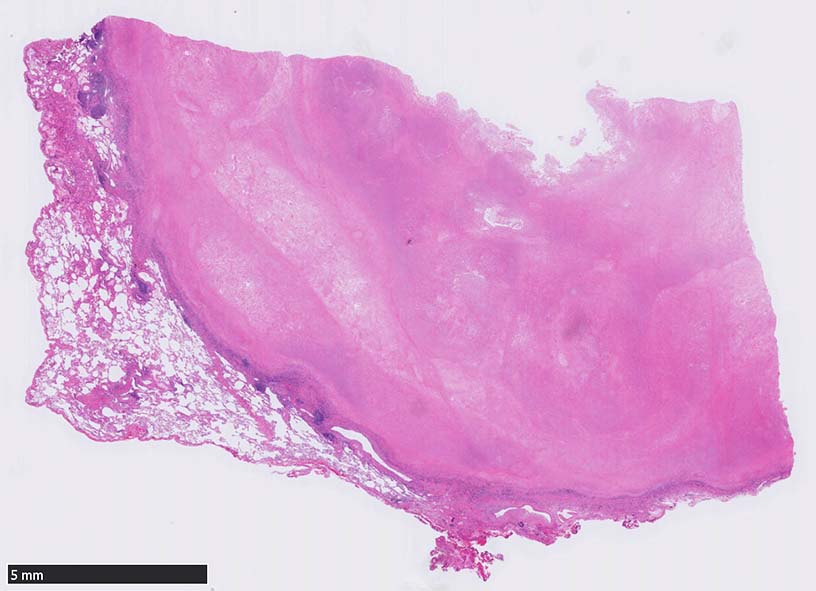

胸膜に近接する25x28mm, 境界明瞭, 黄白色の腫瘤. 滑面は乾酪様で年輪のような縞模様が観察された. 中央部付近に壊死による空洞を認める.

リンパ球が浸潤する肉芽組織を介して胸膜と接着している. 巨細胞は認められない. 炎症細胞浸潤も高度ではない.

空洞辺縁の壊死部分に真菌菌体が認められた.